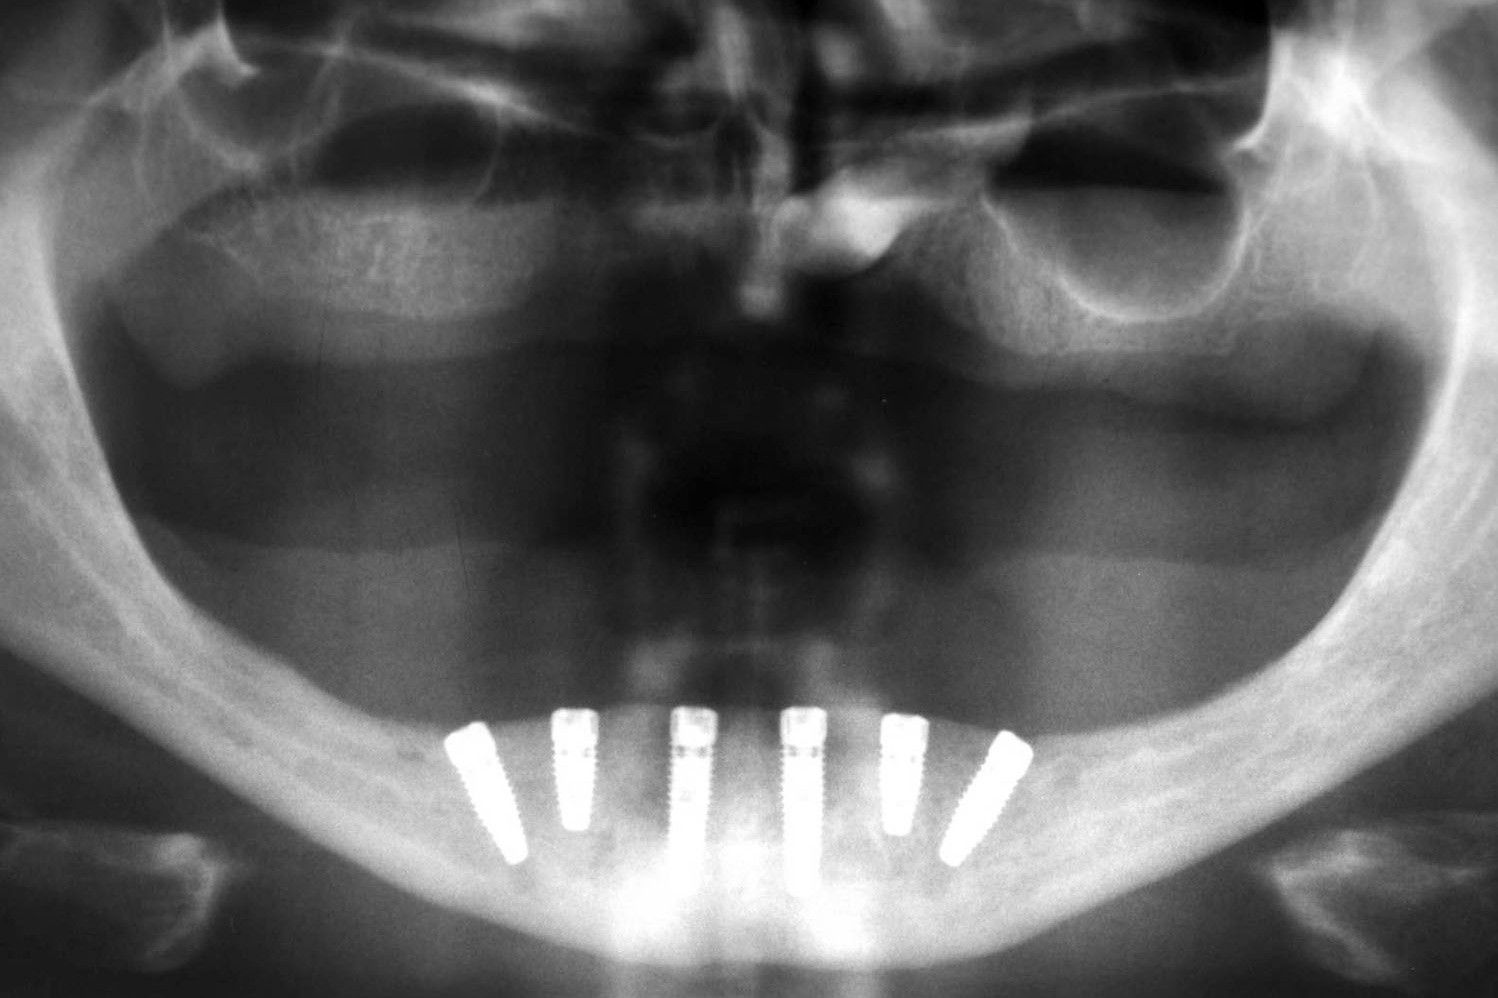

ALL-ON-4

TECHNIKI I PROCEDURY IMPLANTOLOGICZNE STOSOWANE W PRZYPADKU BEZZĘBIA W DOLNYM ŁUKU ZĘBOWYM

Zalety ALL-ON-4:

• Stwarza możliwość wykonania całkowitej rekonstrukcji uzębienia tylko na 4 implantach.

• Pozwala na uniknięcie obciążających zabiegów rekonstrukcji kostnej.

• Skraca czas pełnej rehabilitacji implantoprotetycznej w porównaniu ze standardowymi procedurami, uwzględniającymi zastosowanie implantów osteointegrujących.

• Poprzez użycie pochylonych implantów w odcinkach bocznych pozwala uniknąć uszkodzenia ważnych szczegółów anatomii oraz zwiększa powierzchnię przylegania i osteointegracji implantów z kością.

• Rozwiązania protetyczne w systemie all-on-4 uwzględniają możliwość wykonania stałych prac protetycznych, czyli mostów zamocowanych na stałe, jak również protez ruchomych wspartych jedynie na implantach.

• System umożliwia natychmiastowe obciążenie implantów tymczasowym mostem protetycznym zaraz po założeniu implantów.

• Możliwe jest zastosowanie systemu nawigacji komputerowej NobelGuide, celem precyzyjnego zaplanowania pozycji implantów jeszcze przed zabiegiem chirurgicznym. Dzięki użyciu specjalnych szablonów chirurgicznych możliwa jest implantacja w optymalnych pozycjach, które uwzględniają budowę i niedostatki kości.

• Naukowo udokumentowana skuteczność stosowanej metody.

ROZWIĄZANIA PROTETYCZNE ALL-ON-4

Na implantach wszczepionych zgodnie z protokołem all-on-4 możliwe są do wykonania stabilne mosty, jak również ruchome protezy typu nakładowego. Uproszczenie i optymalizacja rozwiązań protetycznych możliwa jest dzięki zastosowaniu kątowych łączników typu MultiUnit (17°, 30°), które po przykręceniu do pochylonych implantów umożliwiają łatwe mocowanie mostu i obsługę serwisową pacjenta.

Jest to opatentowana metoda rekonstrukcji implanto-protetycznej kompletnego uzębienia stosowana przy bezzębiu zarówno dla dolnego, jak i górnego łuku zębowego. Bazuje na charakterystycznie wszczepionych 4 implantach zębowych, stąd nazwa Wszystko na 4. Dwa środkowe wprowadzane są w kość prostopadle do jej brzegu i równolegle do siebie, dwa boczne wszczepiane są pod kątem 45 stopni. Rozwiązanie protetyczne to most przykręcany na stałe do implantów, który może być zakładany natychmiast po zabiegu implantacji lub w czasie odroczonym. Gwarancją natychmiastowego przywrócenia funkcji żucia jest odpowiednia siła osadzania implantów mierzona dynamometrycznie w trakcie ich wszczepiania oraz należyta staranność wykonania i osadzenia prac protetycznych.